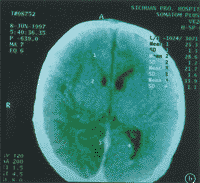

脑血流(CBF)减少是新生儿缺氧缺血性脑病(HIE)的重要原因之一。头颅CT检查可显示HIE患儿脑部的组织形态学变化,SPECT脑血流灌注显像能反映正常新生儿和HIE患儿脑CBF的情况[1-3] 。为了解HIE患儿脑部组织形态学变化与CBF的关系,对35例HIE患儿进行SPECT脑血流灌注显像和CT检查,并作对比分析,现报道如下。

2.方法。SPECT脑血流灌注断层显像按本院常规[2,3] ,检查日龄(7±4)d ......